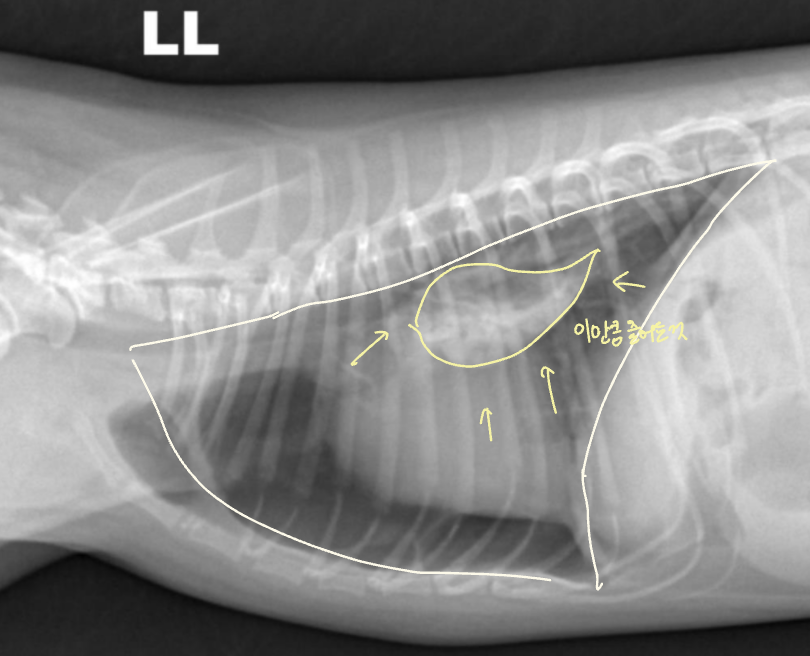

관련 질병 3) Asthma

[Feline Asthma]

- Hyperlucent lung fields; “air-trapping” (까만 폐)

- Tenting diaphragm

- Bronchial patterns (기관지 두꺼워짐, 염증 ↑)